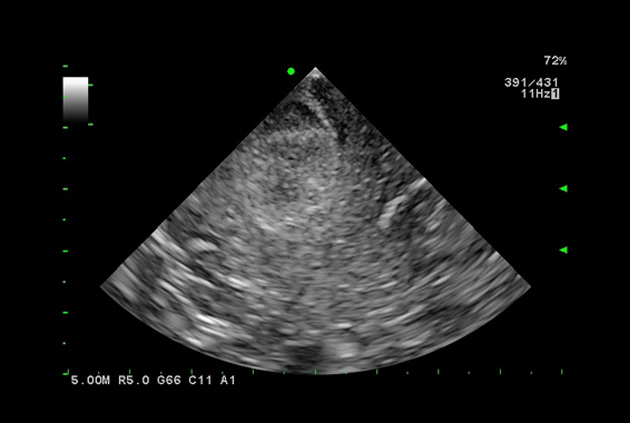

Superior guidance for all applications

Fujifilm Healthcare Americas is committed to designing tools that help surgeons navigate inside the human body and provide the necessary information to immediately make critical surgical decisions.

Fujifilm Healthcare's dedication to Surgeons provides outstanding ultrasound technology, professional support and the specialized tools necessary to best perform comprehensive real-time ultrasound imaging in Breast Surgery, General Surgery, Laparoscopic Surgery, Neurosurgery, Robotic Surgery and Surgical Oncology.

Recognized for our outstanding image quality, outstanding system reliability and intuitive use of cutting edge technology, Fujifilm Healthcare remains the standard in the field of Surgery.

Recognized for our outstanding image quality, outstanding system reliability and intuitive use of cutting edge technology, Fujifilm Healthcare remains the standard in the field of Surgery.